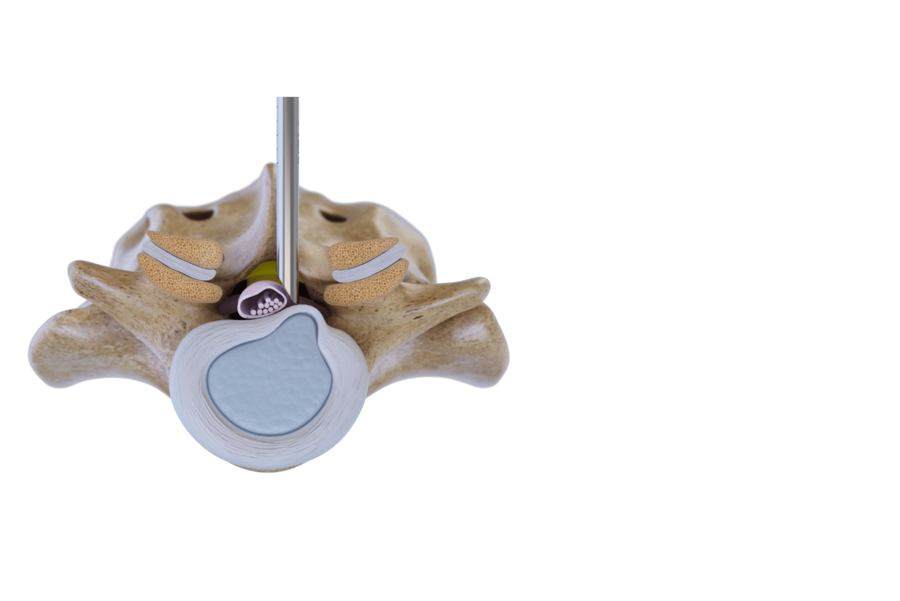

インターラミナ法

インターラミナ法では、椎弓間窓を通じて脊柱管にアクセスします。この方法は、通常 L5/S1 レベル では追加の骨切除無しで行うことが可能です。上位腰椎や狭窄症の場合は、追加の骨切除が必要になります。このテクニックは、脊柱管内のヘルニアや病変 、特に ヘルニアの移動例や狭窄例に最適です。